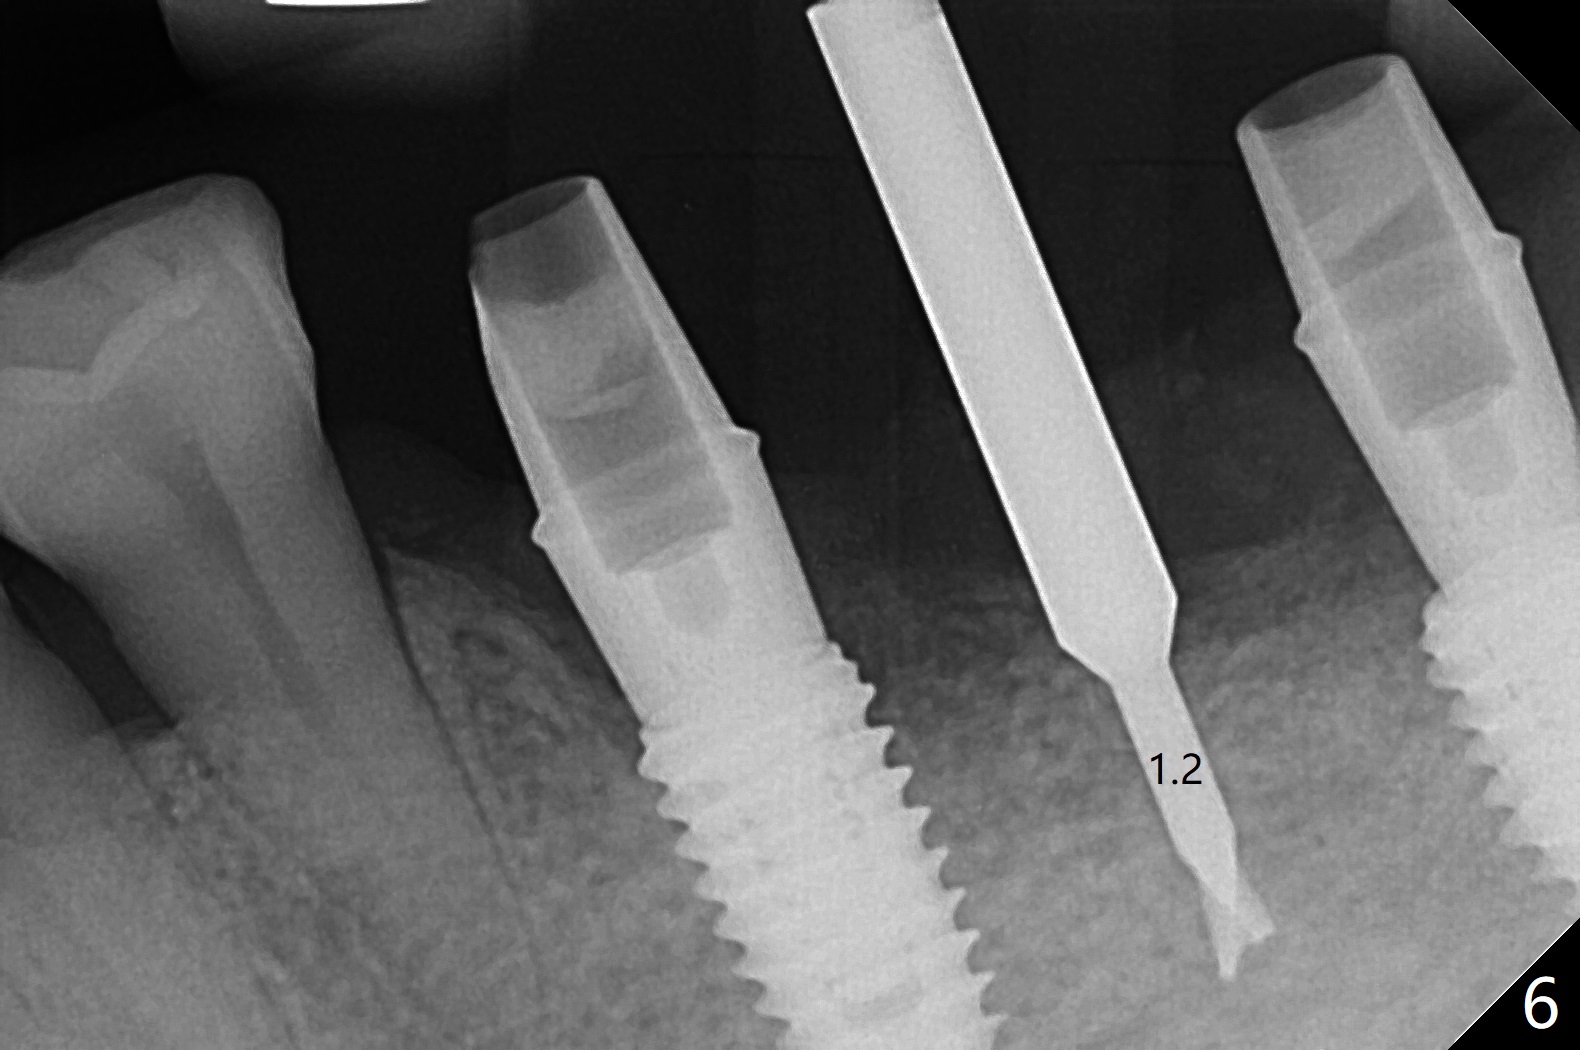

PA is taken after a 2.2 mm drill reaches the depth at #12, since osteotomy is initiated in the mesial slope of the socket (Fig.1 red dashed line) and the neighboring root (*) slightly curves distal. A 8.6x5 mm healing abutment is used to close the socket with the large mesiodistal space after bone graft (Fig.2 *). In contrast, the socket at #20 is large; a 4.5x4.5(3) mm cementation abutment is placed for an immediate provisional to keep autogenous bone (harvested from the site of #18) in place (Fig.3). Six months postop, the patient does not want implant FPD. She wants an additional implant at #19. Since the space between the implants #18 and 20 is 9.41 mm, a narrow implant is indicated (3 or 3.5 mm, Fig.4), in spite of the sufficient buccolingual width (Fig.5). The position and trajectory of the 1.2 mm initial drill and 3x10(2) mm 1-piece implant are acceptable with free hand (Fig.6,7). After 3-4 more turns, panoramic X-ray (Fig.8) and CT (Fig.9) are taken for 28-30 guide. It appears that the 1-piece implant is placed acceptable buccolingual (Fig.9 B). The implants at #12,18,20 (4.5 months postop with guide) are shown in Fig.10-12. It appears that guided surgery is superior in buccolingual position and trajectory to free hand. There is crestal remodeling without implant thread exposure 11 months postop (Fig.13).